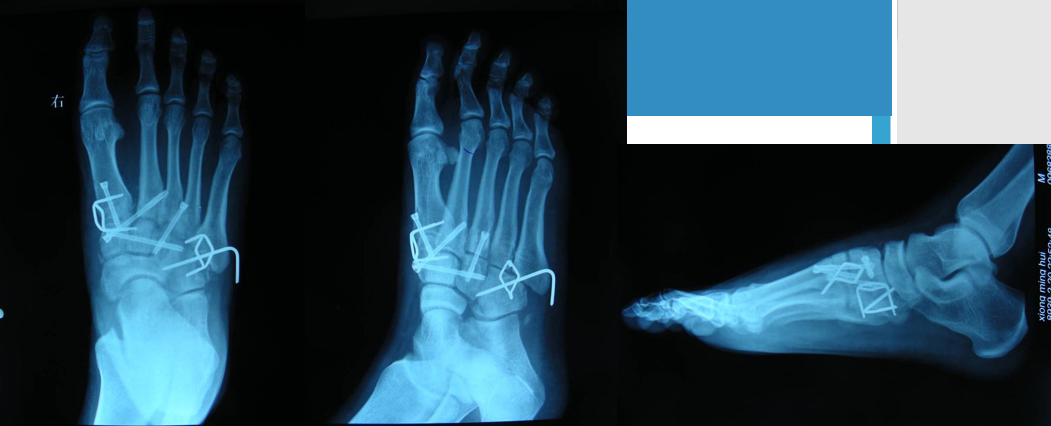

在足正位X线上,第1、2、3跖骨的内外侧缘分别和它相对应的楔骨的内外侧缘呈一直线排列;第一、二跖骨基底间隙和内中楔骨间隙相等。

30°斜位上:1、第四跖骨内侧缘和骰骨内侧缘连续成一条直线2、第三跖骨内侧缘和外侧楔骨内侧缘连续成一条直线3、第二、三跖骨基底间隙和内、中楔骨间隙相等。

侧位上,跖骨不超过相应楔骨背侧缘。从远端的跖骨经过跖跗关节到近端的跗骨,应该是一条不间断的连线

2005年Pearse等提出“ABC”的方法来阅读足部X 线片, 以减少中、前足的漏诊。 A ( alignment)检查跖骨与相应楔骨的对应线 B ( bone)检查每一块骨的轮廓 C ( congruity )检查整体一致吻合, 在正位片上观察内柱, 在斜位片上观察中、外柱。侧位片的常规检查可发现Lisfranc关节矢状面的半脱位及撕脱性骨折

Lisfranc损伤骨折复位标准:1、C形臂透视显示正、侧、斜位均为正常解剖复位2、如复位后第1、2跖骨基底间隙和内、中楔骨间隙<2mm,跖跗骨轴线<15°为近解剖复位,可以接受,超过这个范围的移位则无法接受3、复位好后,沿第一跖骨轴线向内侧楔骨逆行拧入一枚4.0mm皮质骨螺钉。螺钉由关节远侧1.5-2.0cm处进入,平行于足底或略向跖侧。